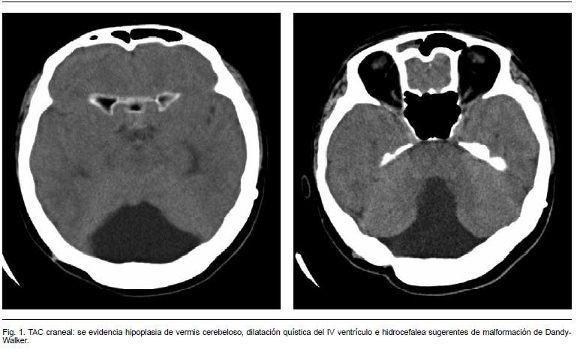

La exploración neurológica mostró un edema de papila bilateral y paresia del VI par derecho. La agudeza visual fue de 20/40 a nivel de ambos ojos. Presentaba una leve rigidez de nuca. La TAC craneal (Figura 1) mostró una hipoplasia del vermis cerebeloso, dilatación quística del IV ventrículo e hidrocefalia, definitorios del diagnóstico de malformación de Dandy-Walker. Se realizó una punción lumbar que puso de manifiesto una hipertensión intracraneal (presión de apertura > 34 mmH2O), con glucosa y proteínas dentro de la normalidad y ausencias de células. El paciente fue sometido a tratamiento neuroquirúrgico, realizándose una combinación de derivación ventrículoperitoneal y quistoperitoneal sin complicaciones. Tras la cirugía se produjo la desaparición de la sintomatología neurológica.